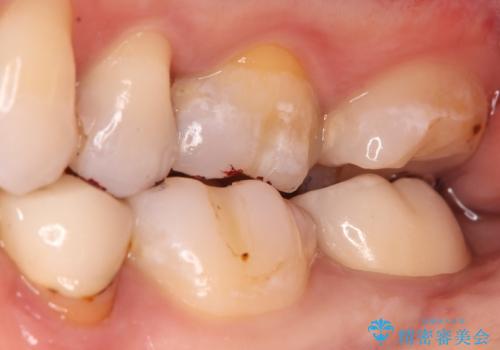

噛み合わせや食べ物の詰まりなどは問題なく、経過良好とのことで満足いただけました。